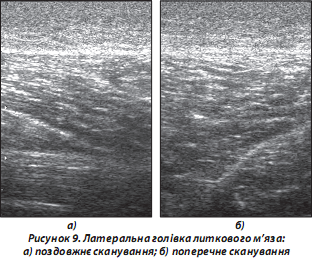

9. М’язові структури — гіпоехогенні порівняно з підшкірно-жировою клітковиною, сухожиллями. Проведення функціональних проб зі скороченням м’язів призводить до зміни ходу м’язових волокон та незначного зниження ехогенності досліджуваного м’яза (рис. 9):

а) поздовжнє сканування: відносно гомогенні гіпоехогенні пучки, окреслені паралельними гіперехогенними утвореннями (сполучнотканинні прошарки — фасції тощо) у вигляді «пера», що поступово переходять у сухожильну частину досліджуваного м’яза [Зубарев А.В., 2002];

б) поперечне сканування: гіпоехогенна дрібно крапчаста структура з гіперехогенними (фіброзними) прошарками та переходом у сухожильну тканину.